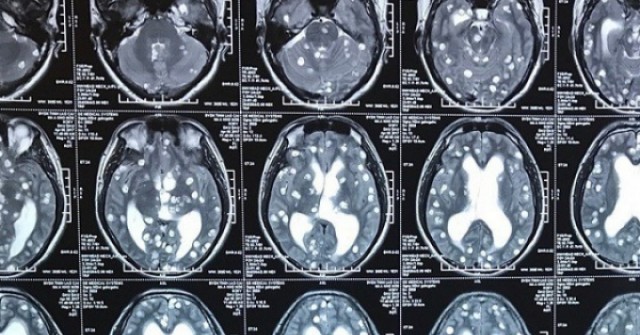

Ngay khi tiếp nhận bệnh nhân, các bác sĩ Bệnh viện Trung ương Quân đội 108 (Hà Nội) thăm khám, chỉ định cho bệnh nhân chụp cắt lớp vi tính và thực hiện các xét nghiệm cần thiết để đánh giá tổn thương. Sau cuộc hội chẩn, chỉ định phẫu thuật cấp cứu để lấy dị vật ra khỏi vùng đầu nhanh chóng được đưa ra.